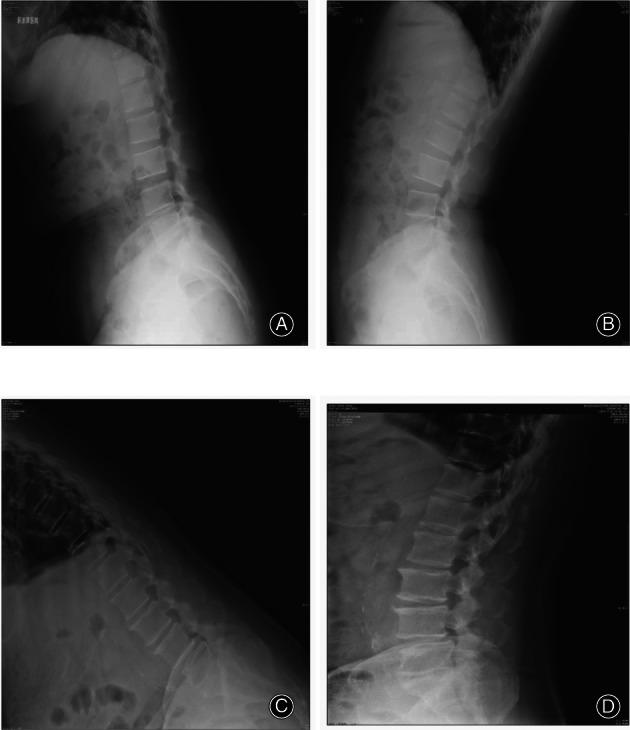

Based on the inclusion and exclusion criteria, the comparative analysis included consecutive patients with grade-1 degenerative spondylolisthesis who underwent oblique LIF (OLIF, n = 36) or minimally invasive transforaminal LIF (MI-TLIF, n = 45) at the Department of Spine Surgery, Beijing Jishuitan Hospital from January 2016 to August 2017. Patient satisfaction Japanese Orthopaedic Association score, visual analog scale (VAS) scores for back and leg pain, Oswestry disability index (ODI), radiographic outcomes including anterior/posterior disc heights (ADH/PDH), foraminal height (FH), foraminal width (FW), cage subsidence, cage retropulsion, and fusion rate were assessed during a 2-year follow-up. Continuous data are presented as mean ± standard deviation and were compared between groups using the independent sample t-test. Categorical data are presented as n (%) and were compared between groups using the Pearson chi-squared test or Fisher's exact test. Repetitive measurement and analysis of variance was employed in the analysis of ODI, back pain VAS score, and leg pain VAS score. Statistical significance was defined as p < 0.05.

The OLIF and MI-TLIF groups comprised 36 patients (age, 52.1 ± 7.2 years; 27 women) and 45 patients (age, 48.4 ± 14.4 years; 24 women), respectively. Satisfaction rates at 2 years post procedure exceeded 90% in both groups. The OLIF group had less intraoperative blood loss (140 ± 36 vs 233 ± 62 mL), lower back pain VAS score (2.42 ± 0.81 vs 3.38 ± 0.47), and ODI score (20.47 ± 2.53 vs 27.31 ± 3.71) at 3 months follow-up (with trends toward lower values at 2 years follow-up), but higher leg pain VAS scores at all postoperative time points than the MI-TLIF group (all p < 0.001). ADH, PDH, FD, and FW improved in both groups post-surgery. At the 2 year follow-up, the OLIF group had a higher rate of Bridwell grade-I fusion (100% vs 88.9%, p = 0.046) and lower incidences of cage subsidence (8.33% vs 46.67%, p < 0.001) and retropulsion (0% vs 6.67%, p = 0.046) than the MI-TLIF group.

OLIF 组和 MI-TLIF 组分别包括 36 例患者(年龄 52.1±7.2 岁,27 例女性)和 45 例患者(年龄 48.4±14.4 岁,24 例女性)。两组术后 2 年的满意度均超过 90%。OLIF 组术中出血量较少(140±36 比 233±62 mL),术后 3 个月时腰痛 VAS 评分(2.42±0.81 比 3.38±0.47)和 ODI 评分(20.47±2.53 比 27.31±3.71)较低(术后 2 年呈下降趋势),但术后各时间点腿痛 VAS 评分均高于 MI-TLIF 组(均 p<0.001)。两组术后 ADH、PDH、FD 和 FW 均得到改善。术后 2 年时,OLIF 组 Bridwell 分级融合率较高(100%比 88.9%,p=0.046),cage 下沉率较低(8.33%比 46.67%,p<0.001)和后移率较低(0%比 6.67%,p=0.046)。